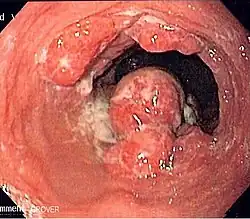

Cancers of the mouth, esophagus, pharynx, and larynx

Alcohol consumption at any quantity is a risk factor for head and neck cancers, such as cancers of the mouth, esophagus, pharynx and larynx.[48]

The U.S. National Cancer Institute states "Drinking alcohol increases the risk of cancers of the mouth, esophagus, pharynx, larynx, and liver in men and women, … In general, risks increases above baseline with any alcohol intake (mild; <2 glass of wine per week) and increases significantly with moderate alcohol intake (one glass of wine per day) with highest risk in those with greater than 7 glasses of wine per week. (A drink is defined as 12 ounces of regular beer, 5 ounces of wine, or 1.5 ounces of 80-proof liquor.) … Also, using alcohol with tobacco is riskier than using either one alone, because it further increases the chances of getting cancers of the mouth, throat, and esophagus."[49]